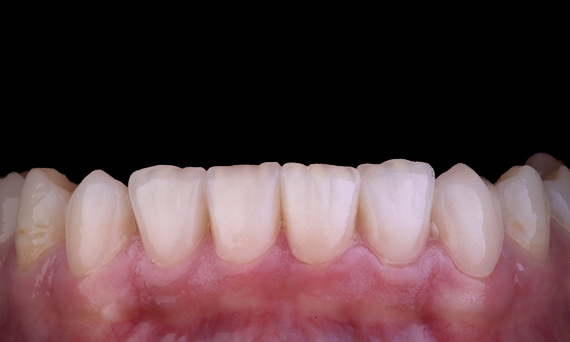

Deze patiënt presenteerde zich met een gebroken restauratie op tand 46 distaal-occlusaal aspect. De bestaande restauratie van de tand reikte zeer diep en dicht bij de pulpakamer. Gezien de grote omvang van de restauratie was het zeer waarschijnlijk dat als we de restauratie gewoon zouden vervangen door een andere directe restauratie, het resultaat hetzelfde zou zijn, waarbij de restauratie onder de occlusale belastingen breekt waaraan de tand en de restauratie worden blootgesteld. Er werd dus een indirecte optie aanbevolen voor de tand. Aangezien het mesiale derde deel van de tand grotendeels niet werd beïnvloed door de resterende substantiële gezonde tandstructuur, konden we deze behouden en minimaal invasief zijn door de tand te herstellen met een indirecte restauratie met behulp van het CEREC-systeem

Dr. Sahil Soni, Queensland, Australië